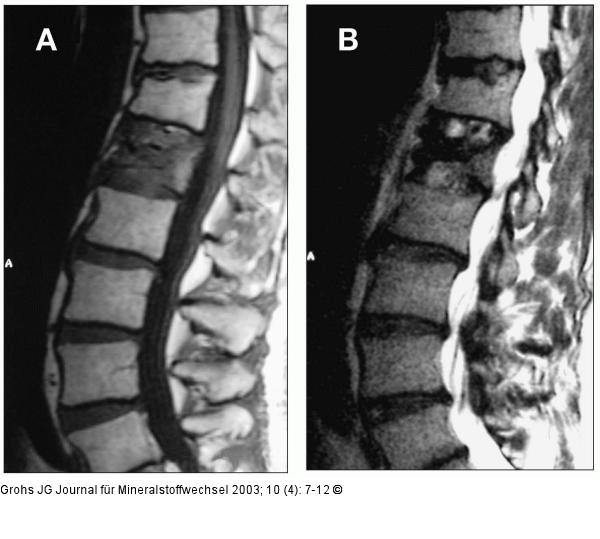

Abbildung 3a-b: Fraktur - hypointens - hyperintens Die Magnetresonanztomographie zeigt die Zeichen einer frischen Fraktur. a) t1-gewichtete MRT mit hypointenser Zone im Wirbelkörper L1; b) t2-gewichtete MRT mit hyperintensem Signal in L1. |

Die Magnetresonanztomographie zeigt die Zeichen einer frischen Fraktur. a) t1-gewichtete MRT mit hypointenser Zone im Wirbelkörper L1; b) t2-gewichtete MRT mit hyperintensem Signal in L1. |